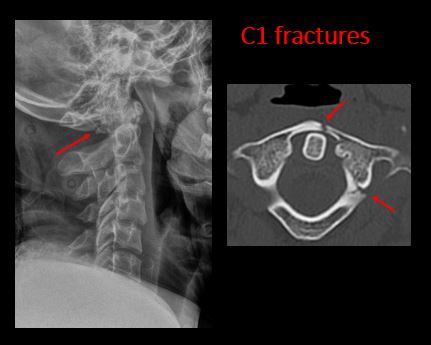

Section 1 Submit Findings C442 Findings Technique The craniocervical junction and/or C7-T1 are not entirely included on the exam. Yes No The exam is over or under penetrated. Yes No The exam is limited by overlying structures, bones or soft tissues, body habitus, patient positioning, support devices, or motion. Yes No Prevertebral and paravertebral soft tissues The soft tissues anterior to C1-C7 are widened or the prevertebral fat stripe is not seen. Yes No The paravertebral soft tissues are abnormally widened. Yes No N/A There is calcification, foreign body, abnormal air, or other abnormal density in the prevertebral or paravertebral soft tissues. Yes No Spinal alignment The distance between the basion and the posterior axial line is > 12 mm. Yes No The distance between the basion and the tip of the dens is > 12 mm. Yes No The atlanto-axial joint distance is > 2 mm on the lateral view. Yes No The distance between the dens and the lateral masses of C1 is abnormally asymmetrically widened on an odontoid or AP view. Yes No N/A The lateral mass(es) of C1 abnormally override(s) the articular pillar(s) of C2 on an odontoid or AP view. Yes No N/A The anterior vertebral body line, posterior vertebral body line, articular pillar line, and/or spinolaminar line is/are abnormal. Yes No The articular pillars or lateral masses, lamina, or other posterior elements are rotated or displaced into the spinal canal or the interlaminar clear zone of the spinal canal. Yes No The visualized spinous processes are malaligned on the AP view or distracted on the lateral view. Yes No There is reversal or straightening of the normal lordosis or abnormal angulation/curvature or motion of the cervical spine on frontal, lateral, flexion and/or extension views. Yes No Vertebral bodies, posterior elements, and base of skull There is a fracture or deformity of the base of the skull or occipital condyles. Yes No There is a fracture or deformity of the anterior or posterior arch of C1. Yes No There is a fracture or deformity of the lateral mass(es) of C1. Yes No There is a fracture or deformity of the dens or C2 vertebral body. Yes No There is a fracture or deformity of the pars interarticularis/articular pillars or other posterior elements of C2. Yes No There is a fracture or distraction of a C3-T1 vertebral body, transverse or spinous process, or other posterior element. Yes No There is evidence of an end plate avulsion or other fracture. Yes No There is displacement of a fracture fragment into the soft tissues, spinal canal, or interlaminar clear zone of the spinal canal. Yes No There is anterior wedging or compression of a vertebral body or end plate. Yes No There is evidence of an aggressive disease process manifest as a lytic, sclerotic, or destructive abnormality of a vertebral body, end plate, pedicle, lamina, articular pillar, transverse or spinous process. Yes No There is focal or diffuse abnormal mineralization. Yes No Disc spaces and facet joints There is distraction or focal widening of a disc space. Yes No There is anterolisthesis, retrolisthesis, subluxation, or rotational abnormality of a disc space. Yes No There is widening, rotational abnormality, or displacement of facets at any motion segment (e.g. locked or jumped, perched facets, or fracture dislocation). Yes No There is disc space narrowing with or without erosive or sclerotic changes of the end plates other than from degenerative change. Yes No There is facet joint narrowing or sclerosis other than from degenerative change. Yes No Additional soft tissues and bones (neck, airway, upper thorax, ribs) The included maxillofacial region, thoracic spine, ribs, or other bones of the upper thorax are abnormal. Yes No There is air or a foreign body or other abnormality in the soft tissues of the lower head, neck or upper thorax. Yes No There is an apical mass, thickening, pleural cap or effusion, or pneumothorax. Yes No N/A The airway is narrowed or displaced. Yes No There are post surgical changes of the bones or soft tissues of the lower head, neck, or upper thorax. Yes No There is an abnormality or complication of post-surgical hardware. Yes No N/A There are support lines or tubes in an abnormal position. Yes No Other findings There are degenerative changes or other existing conditions that might be contributing to symptoms which can or should be further evaluated non-emergently. Yes No